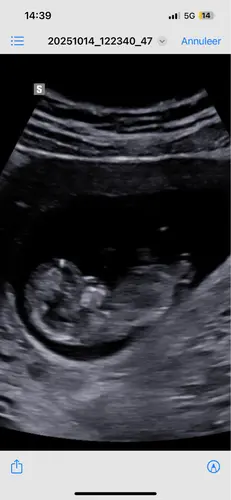

Eerlijk gezegd, kan ik bij alle onderstaande foto’s niets uithalen.. ze zijn te wazig, nub niet goed zichtbaar

Wat denken jullie?

Ik ben een nub-noob dus wil ook graag bij de andere dames checken of ik geen onzin uitkraamt: je ziet de nub hier goed (als het ten minste de nub is en niet een stuk van het linkerbeentje) en op basis van de hoek met de ruggenwervel zou dit een meisje zijn.